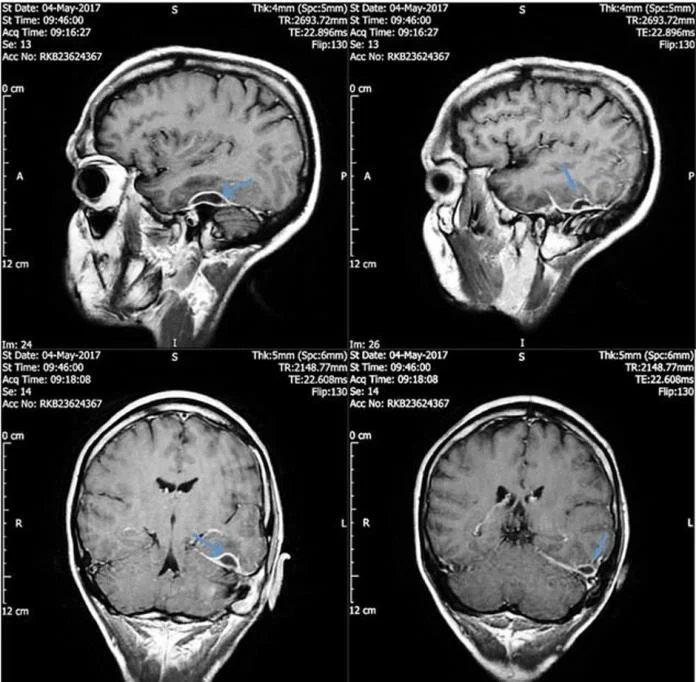

Izvukli su vatu muškarcu iz uha i dijagnosticirali mu rijetku upalu zvanu nekrotizirajući otitis. Infekcije uha obično uzrokuje bakterija i pogađaju kanal uha i okolnu kost, ili kao kod ovog pacijenta i okolno tkivo, ali ne i mozak. Snimke su pokazale da se kod njega stvorio gnoj između kosti lubanje i mozga.

Nakon šest dana intravenoznog antibiotika, količina gnoja se smanjila. Neimenovani pacijent se potpuno oporavio za deset tjedana. Doktori su napisali da je tura antibiotika izliječila upalu te da pacijent nije imao daljnjih neuroloških problema.